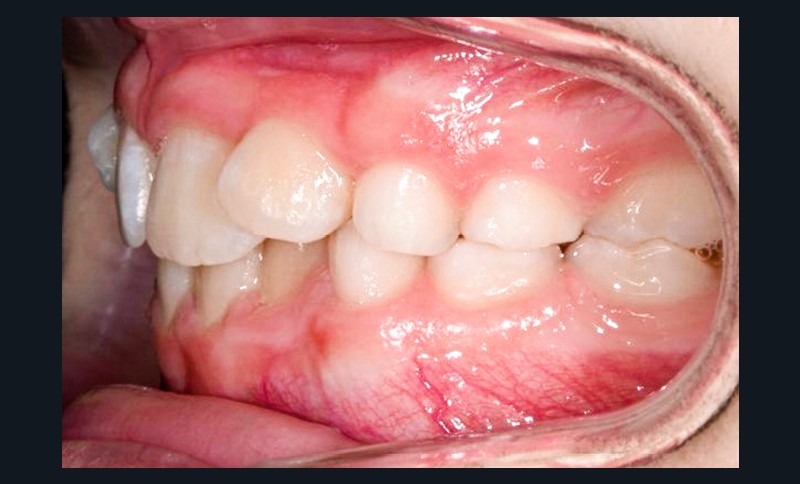

L’appareil est déposé après la mise en place de contentions collées de 12 à 22 et de 33 à 43 avec le port nocturne d’une plaque de Hawley à l’arcade maxillaire. Le temps de traitement actif a été de 41 mois.